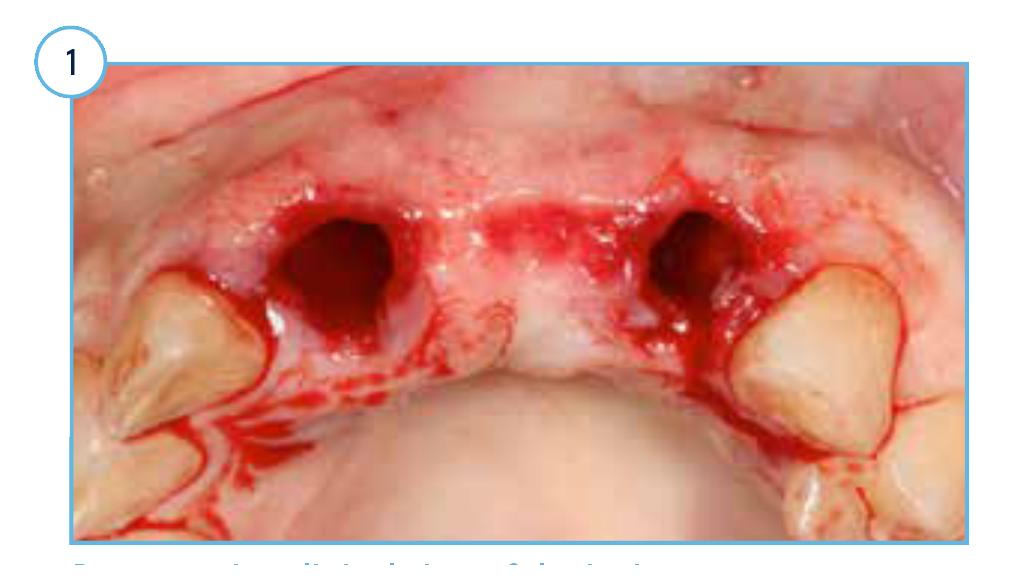

TSVT Implants (4.1 mm x 16 mm) with attached fixture mounts threaded into the prepared extraction sockets.